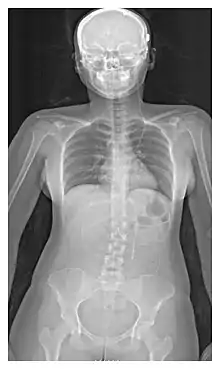

Shunt location

The location of the shunt is determined by the neurosurgeon based on the type and location of the blockage causing hydrocephalus. All brain ventricles are candidates for shunting. The catheter is most commonly placed in the abdomen but other locations include the heart and lungs.[10] Shunts can often be named after the route used by the neurosurgeon. The distal end of the catheter can be located in just about any tissue with enough epithelial cells to absorb the incoming CSF. Below are some common routing plans for cerebral shunts.

Shunt routing

Route | Location of fluid drain |

---|---|

Ventriculo-peritoneal shunt (VP shunt) | Peritoneal cavity |

Ventriculo-atrial shunt (VA shunt) | Right atrium of the heart |

Ventriculo-pleural shunt (VPL shunt) | Pleural cavity |

Ventriculo-cisternal shunt (VC shunt) | Cisterna magna |

Ventriculo-subgaleal shunt (SG shunt) | Subgaleal space |

Lumbar-peritoneal shunt (LP shunt) | Peritoneal cavity |